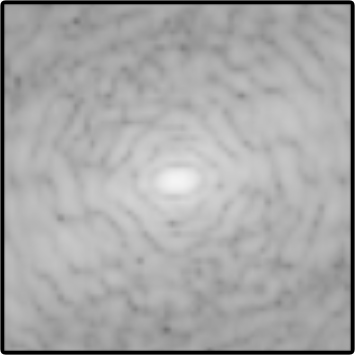

Objectives: Present a novel deep learning-based skull stripping algorithm for magnetic resonance imaging (MRI) that works directly in the information rich k-space. Materials and Methods: Using two datasets from different institutions with a total of 36,900 MRI slices, we trained a deep learning-based model to work directly with the complex raw k-space data. Skull stripping performed by HD-BET (Brain Extraction Tool) in the image domain were used as the ground truth. Results: Both datasets were very similar to the ground truth (DICE scores of 92\%-98\% and Hausdorff distances of under 5.5 mm). Results on slices above the eye-region reach DICE scores of up to 99\%, while the accuracy drops in regions around the eyes and below, with partially blurred output. The output of k-strip often smoothed edges at the demarcation to the skull. Binary masks are created with an appropriate threshold. Conclusion: With this proof-of-concept study, we were able to show the feasibility of working in the k-space frequency domain, preserving phase information, with consistent results. Future research should be dedicated to discovering additional ways the k-space can be used for innovative image analysis and further workflows.